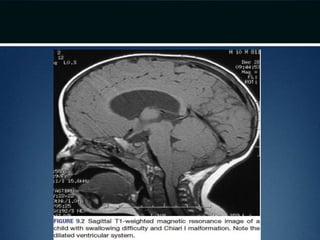

Clinical presentation..

• Pertaining to brainstem, cerebellar and spinal cord dysfunction

• Usualy present in infancy/early childhood

• Worst outcome if symptoms appear before 3 months age

• Stridor, apnea and dysphagia resulting in aspiration  might cause

death

• Nystagmus – earliest sign of cerebellar dysfunction

• Initial spinal cord symptoms (weakness, bowel and bladder

dysfunction) – secondary to inadequate formation of the lower spinal

cord

Diagnosis

• MRI – cranial and spinal

• Plain dynamic cervical spine radiographs

 instability

Clinical presentation.. • Pertainingto brainstem, cerebellar and spinal cord dysfunction • Usualy present in infancy/early childhood • Worst outcome if symptoms appear before 3 months age • Stridor, apnea and dysphagia resulting in aspiration  might cause death • Nystagmus – earliest sign of cerebellar dysfunction • Initial spinal cord symptoms (weakness, bowel and bladder dysfunction) – secondary to inadequate formation of the lower spinal cord

Diagnosis • MRI –cranial and spinal • Plain dynamic cervical spine radiographs  instability